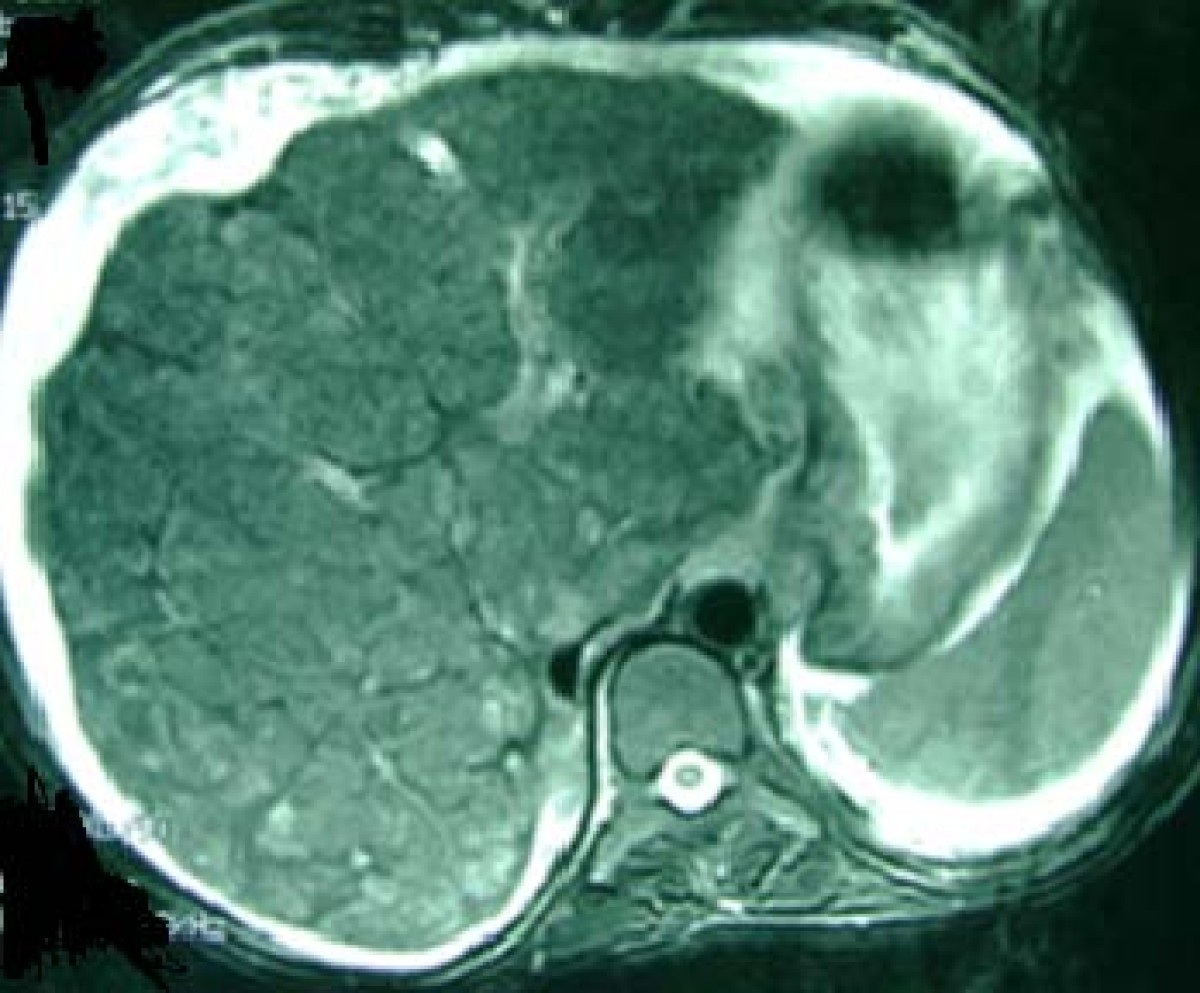

Figure 1 from Congenital hepatic fibrosis case report and review of Congenital Hepatic Fibrosis Case Report And Review Of Literature Congenital hepatic fibrosis (chf) is a rare, autosomal recessive disorder, clinically characterized by hepatic fibrosis and portal hypertension. Chf results from ductal plate. Congenital hepatic fibrosis (chf) is a rare autosomal recessive disease derived from biliary dysgenesis secondary to ductal plate. Congenital hepatic fibrosis is a hereditary fibropolycystic disease caused by ductal plate malformation. Congenital hepatic fibrosis is a hereditary. Congenital Hepatic Fibrosis Case Report And Review Of Literature.